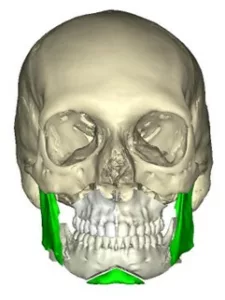

L’ostéotomie de transposition du menton appelée aussi « Génioplastie »

Elle permet de déplacer le menton dans les trois dimensions de l’espace.

La génioplastie peut être réalisée sans ou avec une ostéotomie sagittale des branches montantes.

Les ostéotomies combinées

Elles permettent d’agir simultanément sur l’ensemble des éléments anatomiques de la face. En pratique toutes les combinaisons d’ostéotomies sont possibles selon l’anomalie observée. L’ostéotomie Bimaxillaire avec Génioplastie est la plus courante. Elle associe une ostéotomie de Lefort 1 en un ou plusieurs fragments, une ostéotome sagittale bilatérale des branches montantes et une génioplastie.

Des miniplaques en titane sur mesure spécifiques de l’anatomie propre à chaque patient et spécifiques des mouvements envisagés par le chirurgien permettent de stabiliser toutes les pièces anatomiques libérées par les manœuvres d’ostéotomie conformément à la simulation : plateau maxillaire, arc denté mandibulaire, branches montantes et condyles, menton .